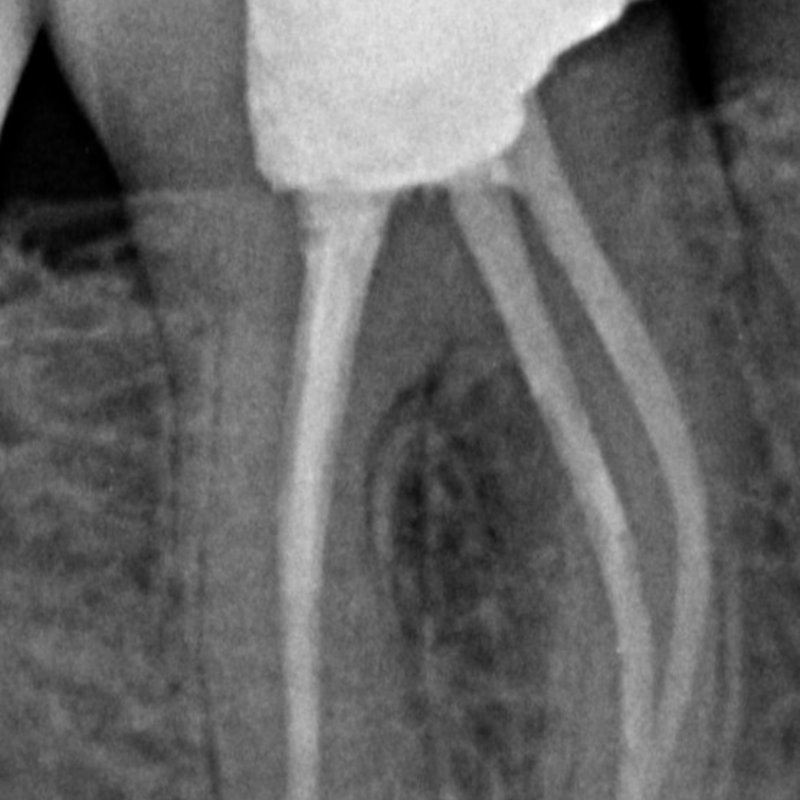

X-ray before root canal treatment

Before After

Root Canal Therapy

Endodontic treatment

Rotary endodontics with apical seal — pre- and post-treatment radiographs showing complete obturation of the canal system.